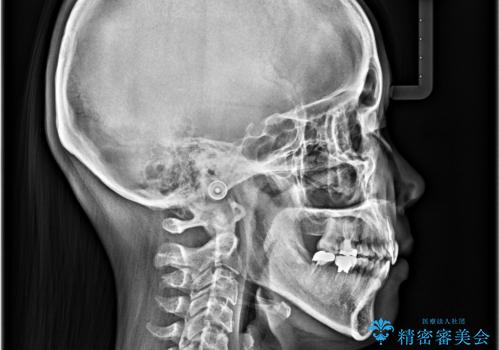

急速拡大装置 狭い骨幅を拡大した上で、顕著なデコボコを改善する抜歯矯正治療

上顎骨よりも下顎骨の幅が広く、更には下顎骨が左側に変位していたため、より良い咬み合わせを達成することを目的として、急速拡大装置を用いて上顎骨を拡大することとしました。

デコボコが強い上に、口元の突出感も気にしていたため、上下左右の小臼歯4本を抜歯して、ワイヤー装置にて矯正治療を行うこととしました。

歯根露出が顕著であったため、歯の移動は早く、スムーズに治療を終えられるかと思いましたが、歯槽骨が硬く、治療は長期間に及びました。

それでも当初とは比べものにならないほど、綺麗な歯列に仕上げることができました。